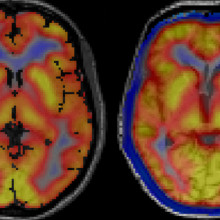

Images captured using a hybrid PET/MRI machine show activated immune cells in the frontal brain regions in a patient with frontotemporal dementia (right) compared to a healthy volunteer (left).

“A presence in those parts of the brain would suggest that inflammation is not playing its normal role of cleaning up damaged cells,” explains Dr. Finger. “It would suggest the brain’s immune response is overactive and that we should consider clinical trials for medications that modulate this response.”